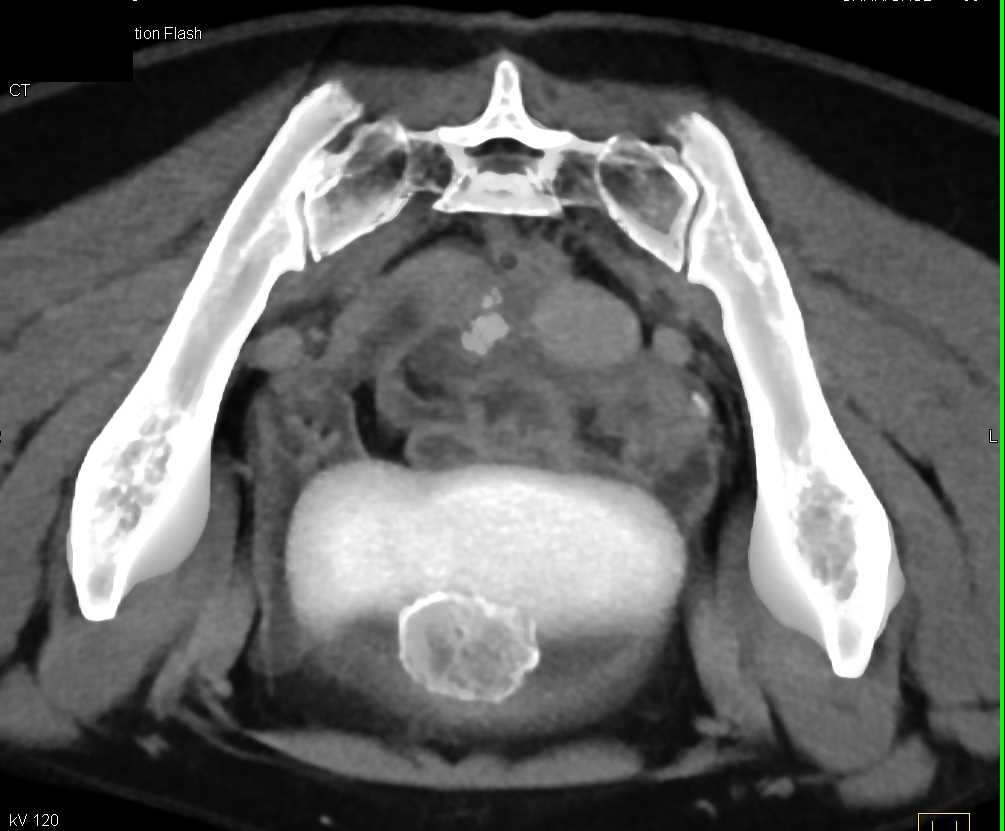

Urachal Carcinoma of the Bladder